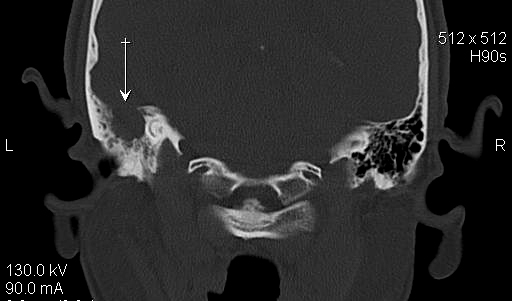

TC exostosis occipital congénica.

TC exostosis occipital congénita.